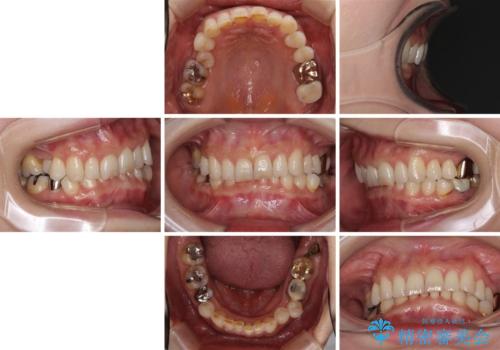

デコボコの歯とむし歯 インビザライン矯正治療とむし歯治療

- 50代女性

- 矯正装置

- 治療期間

- 5年8ヶ月

- 治療回数

- 30回以上

- 治療費の目安: 130万円(税込)費用は治療当時の料金となります